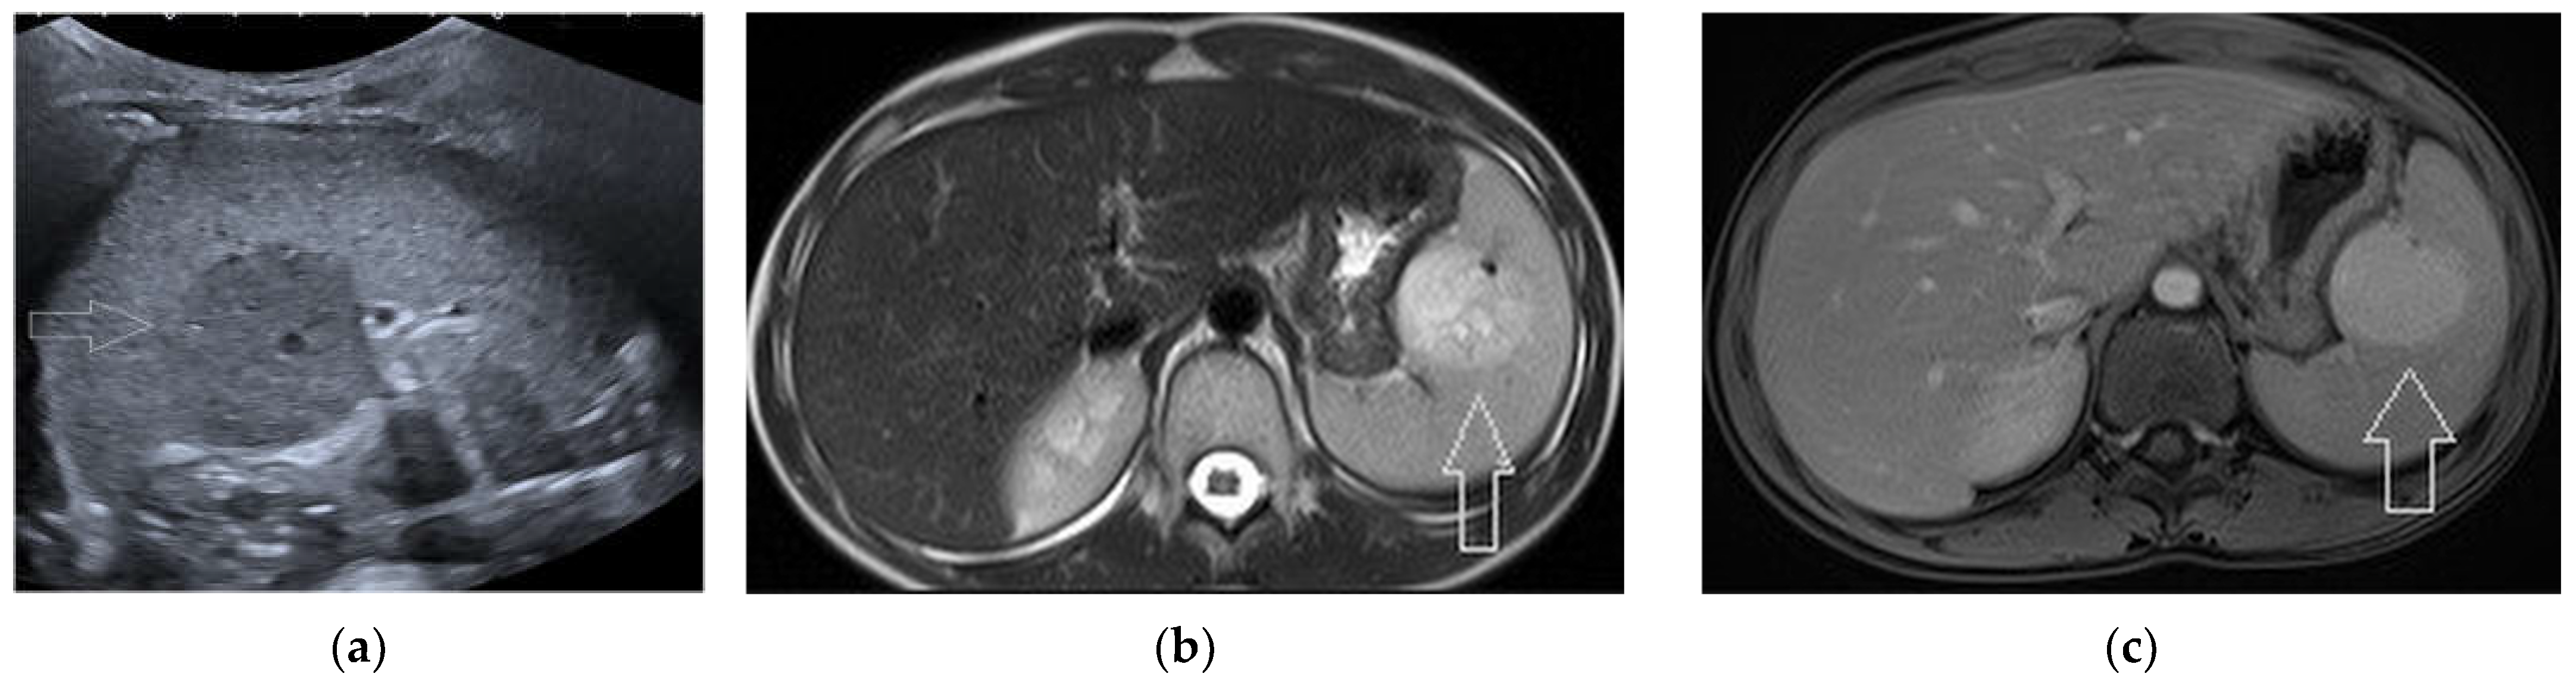

2.7. Solid Lesions

3. Risk of Malignancy and Pattern Recognition